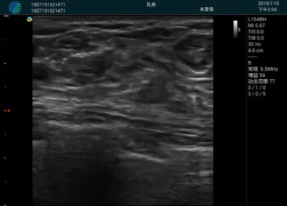

腺體內(nèi)部清晰顯示一低回聲塊影,形態(tài)不規(guī)則,邊界模糊,邊緣呈毛刺狀,內(nèi)部見砂礫樣鈣化

M20引導(dǎo)下穿刺活檢術(shù)

M20引導(dǎo)下平面內(nèi)穿刺取出的腫塊組織